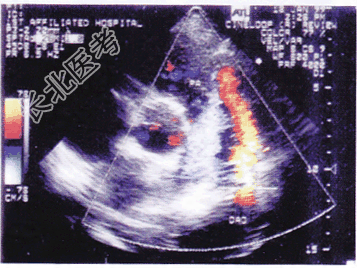

- 单项选择题如图大动脉短轴所示,该病例最有可能的诊断为

A、肺动脉内径增宽

B、动脉导管未闭

C、肺动脉瓣狭窄

D、肺动脉瓣关闭不全

E、右心室流出道狭窄